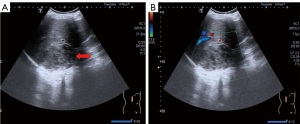

To evaluate the right adrenal mass, the patient underwent an adrenal ultrasound and computed tomography (CT) scans following admission. Ultrasound findings revealed a heterogeneous hypoechoic lesion in the right adrenal region, measuring approximately 8.0 cm × 6.5 cm, with well-defined boundaries and an irregular shape (Figure 2A). The blood flow signal within the lesion was classified as Adler grade 0 (Figure 2B), suggesting a benign adrenal tumor, most likely an adenoma. CT imaging (Figure 3) revealed a rounded low-density mass in the right adrenal gland with clear boundaries and smooth margins (Figure 3A,3C), measuring approximately 7.9 cm × 8.6 cm. The mass exhibited mild enhancement on contrast imaging (Figure 3B,3D), and the CT findings were consistent with a benign tumor, with differential diagnoses including adenoma and ganglioneuroma.

ACL shares similarities with other adrenal lymphangiomas, as it typically presents with few abnormalities in history, symptoms, signs, and adrenal hormone levels, with preoperative diagnosis primarily relying on imaging studies. In the present case, the patient exhibited a low testosterone level, which normalized postoperatively. After analysis, we surmise that this might be attributed to the tumor’s pressure on surrounding tissues or its effect on adrenal blood flow, which could interfere with hormone synthesis. While the adrenal gland primarily produces corticosteroids and catecholamines, tumors can also indirectly affect testosterone levels. The widespread use of ultrasound is crucial for detecting adrenal lesions. Herein, the preoperative ultrasound revealed a heterogeneous hypoechoic mass without significant cystic features, likely due to the small size of the ACL’s cystic spaces and sponge-like characteristics. CT imaging is the preferred method for preoperative diagnosis of adrenal lymphangiomas, typically showing a unilocular, round or oval structure, often revealing cyst walls and septations. Our CT findings indicated a rounded low-density adrenal mass without septations and mild enhancement, suggesting a small cystic cavity in the ACL. The imaging findings from the external hospital MRI and our hospital CT were inconsistent with the final pathological results, highlighting the limitations of imaging in diagnosing rare or complex lesions. Clinically, integrating multiple imaging modalities is warranted to obtain more comprehensive diagnostic information and improve the accuracy of preoperative assessment.